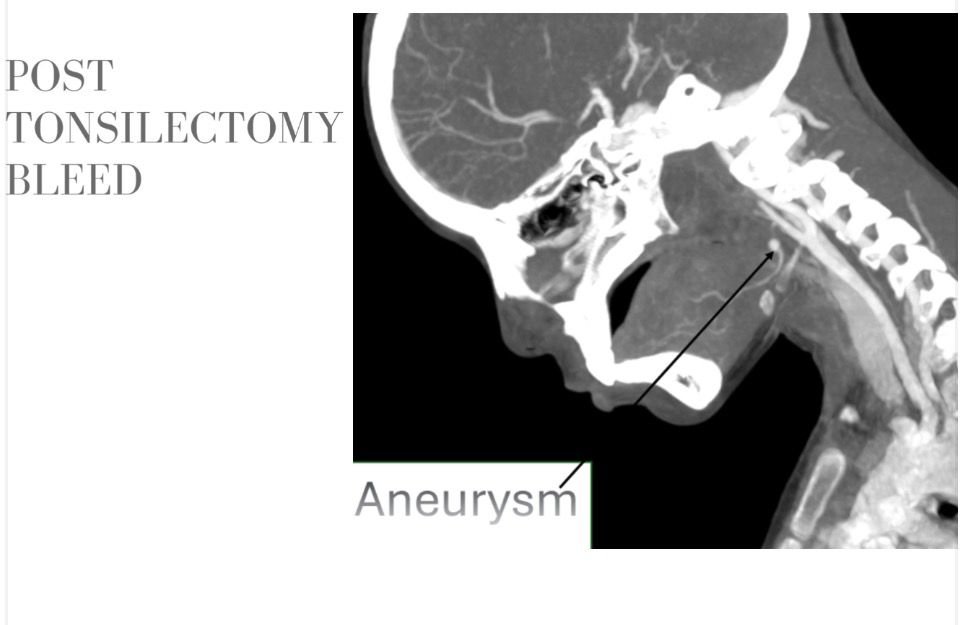

وأكد الدكتور حسان النعماني رئيس الجامعة، أن سرعة التشخيص ودقة التدخل كانتا عاملين حاسمين في إنقاذ حياة الطفلة، مشيرًا إلى أن جاهزية مستشفيات سوهاج الجامعية والتكامل بين أقسامها المختلفة أسهما في التعامل الفوري مع الحالة وفق أحدث الأساليب العلاجية. وأضاف أن فريق الأشعة التداخلية أجرى الفحوصات والأشعات اللازمة فور وصول الطفلة، والتي كشفت عن وجود تمدد شرياني نازف بأحد الشرايين الرئيسية بالرقبة في جدار الحلق، ما تطلب تدخلاً عاجلاً عالي الدقة.